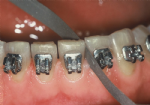

Die festsitzende Apparatur besteht normalerweise aus sogenannten Brackets, die auf die Zähne geklebt werden. Auf die Mahlzähne werden wegen der besseren Verankerungsmöglichkeit manchmal statt der Brackets ringförmige Bänder mit aufgeschweißten Röhrchen zementiert. In diese Bänder und Brackets werden hochelastische Drahtbögen eingesetzt, die die Zähne allmählich in die gewünschte Bogenform bewegen. Zusätzlich werden, je nach Erfordernis, Hilfsteile (elastische Ketten, Zug- und Druckfedern), verwendet. Daneben gibt es Sonderformen festsitzender Apparaturen, wie zum Beispiel festzementierte Platten für die Gaumennahterweiterung, Teilapparaturen auf wenigen Zähnen, und andere, die in ganz bestimmten Situationen Verwendung finden.